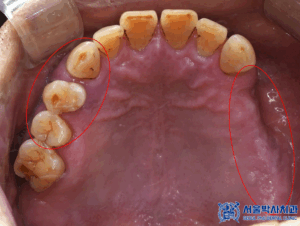

왼쪽 아래 사랑니를 포함한 큰어금니는

맞닿는 위 치아가 없어

정출되어 있는 상황이였고

왼쪽 위는 치아가 없을 뿐 아니라

골흡수가 심하게 진행되어

상악동과의 거리가 가까워져

뼈가 부족한 상황이었습니다.

또한 오른쪽 위 어금니들 역시

치아를 지탱하는 잇몸뼈가

많이 흡수되어 있는 것이

확인되었습니다.